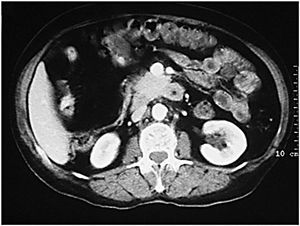

Desde el punto de vista tomodensitométrico (fig. 12) y de la RM los criterios semiológicos son más o menos similares: el engrosamiento mural y la hiperemia característica de una situación inflamatoria activa. Se describe el hecho de que el engrosamiento mural del colon suele ser más marcado en la colitis granulomatosa que en la ulcerosa, lo mismo que la irregularidad de los contornos, que suele ser también más acentuada en los casos de colitis granulomatosa.

Fig. 12.--Enfermedad de Crohn. A) La tomografía computarizada (TC) muestra la afectación del colon de carácter segmentario.(B) En la reconstrucción en plano coronal (MPR) puede apreciarse el marcado engrosamiento mural del colon descendente.